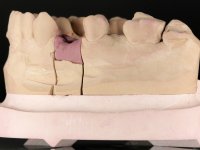

Patient was proposed extraction of the root of the 1.4 tooth, and immediate placement of an implant in its place. Confirmation of this rehabilitation proposal would always be dependent on prior accomplishment of a Computed Axial Tomography, in order to evaluate the available bone heritage. Provisionalization of the edentulous space would be done with a temporary fixed prosthesis bonded to adjacent teeth. This prosthesis would be prepared at the laboratory and would consist of an acrylic prosthetic tooth with an included metal wire that would serve as a retention element. In this way the esthetic problem was solved during osseointegration, avoiding the use of a removable prosthesis. The implant would eventually be rehabilitated with a screwed metal-ceramic crown.

A CT scan was performed to evaluate the available bone heritage and to choose the type and size of implant to be placed. An impression of both jaws was made in alginate, as well as intermaxillary recording for laboratory work on a provisional prosthesis. The provisional prosthesis was made by including a metal wire in a prosthetic tooth adapted to the edentulous space. The root was carefully removed and the implant was placed in the tooth socket corresponding to tooth 1.4. The remaining space between the walls of the alveolus and the implant was filled with regenerative material and then sutured. The prosthesis was previously adapted to the postoperative zone and was then bonded to adjacent teeth. Teflon was used to promote the best possible insulation. Bonding was done using photopolymerizable composite resin using the palatine and inter-proximal walls of the adjacent teeth. After 10 days, the suture was removed and one month later osseointegration was confirmed. Exposure of the implant and placement of the healing screw was performed after 10 weeks. The cervical portion of the provisional tooth had to be reduced to accommodate the healing screw. Stabilized peri-implant soft tissues were impressed using open tray technique with soft and regular consistency putty silicon. In the laboratory the work model was made, along with the choice of pre-fabricated components for the confection of a metal-ceramic crown screwed to the implant with the brand’s interface. Removal of the provisional bridge was done with great care not to touch the interproximal surfaces of the teeth adjacent to the edentulous space. The crown was screwed to the implant, and after imaging, the seating was given the final tightening with 35N of torque. The screw access hole was filled with Teflon and closed with composite resin. The patient manifested satisfaction with the aesthetic and functional rehabilitation achieved.